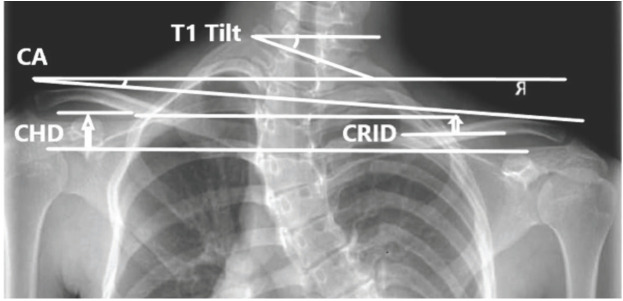

Materials and methods: This observational study recruited 50 patients with adolescent idiopathic scoliosis who were 12 to 18 years of age with Cobb angle >10°. Based on Pearson correlation coefficient, radiographic parameters such as coracoid height difference (CHD), clavicle rib intersection distance (CRID), clavicle angle (CA), clavicle chest cage angle difference (CCAD), and T1 tilt angle were evaluated in correlation with clinical shoulder and neck balance by difference of inner shoulder height (SHi), difference of outer shoulder height (SHo), and neck tilt angle.